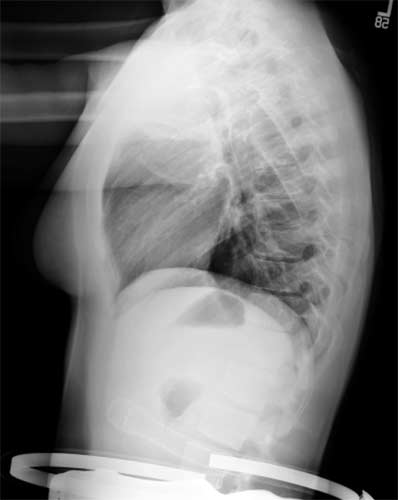

Lateral chest on a normal female.

Note: Images are shown for illustrative purposes. Do not attempt to draw conclusions or make diagnoses by comparing these images to other medical images, particularly your own. Only qualified physicians should interpret images; the radiologist is the physician expert trained in medical imaging.